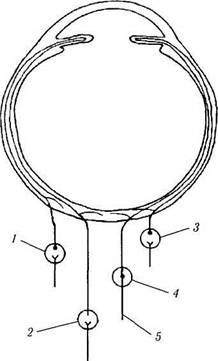

Иннервация сосудистой оболочки. Сосудистая оболочка иннервируется симпатическими и парасимпатическими волокнами, исходящими из ресничного, тройничного, крылонебного и верхнего шейного ганглиев (рис. 3.8.57). В глазное яблоко поступают они с ресничными нервами.

Рис. 3.8.57. Особенности вегетативной иннервации уве-ального тракта глаза:

/ — крылонебный ганглий; 2 —верхний шейный симпатический

ганглий; 3 — ресничный ганглий; 4 — тройничный ганглий; 5 —

пятый нерв